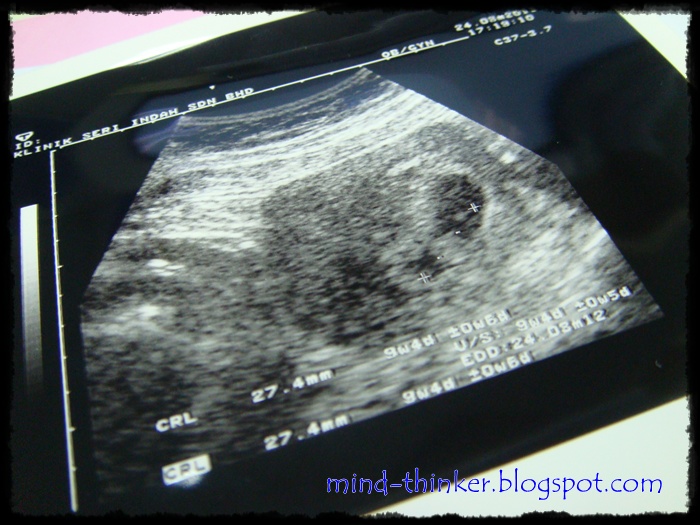

Semalam my pregnancy genap 10 minggu.

Memang dari bulan lepas cadang nak scan minggu ni.

So, Balik keje semalam terus singgah Klinik Seri Indah, Taman Samudera.

Memang klinik ni macam selesa sket pada aku sebab doktor2 pakarnya semua perempuan.

Lepas je register, 5 minit macam tu dah kena panggil.

Masuk bilik doktor terus cakap nak scan.

Pegi bilik sebelah, baring atas katil tu & doktor start scan.

Masa tu....

I am really speechless!

Sungguh pun tak nampak jelas.

Sebab doktor cakap takde air kencing, so susah nak nampak.

Tapi bentuknya tetap la kelihatan.

Doktor: "Aaa, doktor nampak dah heartbeat dia"

Me: *Terdiam sambil tercari2 mana denyutnya*

Doktor: "Takpe, doktor nampak. Doktor tau la.. :)"

To my precious little baby..

Membesar dengan sihat ok.

Nanti ibu & abah nak tengok lagi bulan depan.

Abah nampak samar2 tu pun dia dah terdiam, happy tak terkata.

Kalau nampak betul nanti, pitam terus agaknya, hehe..